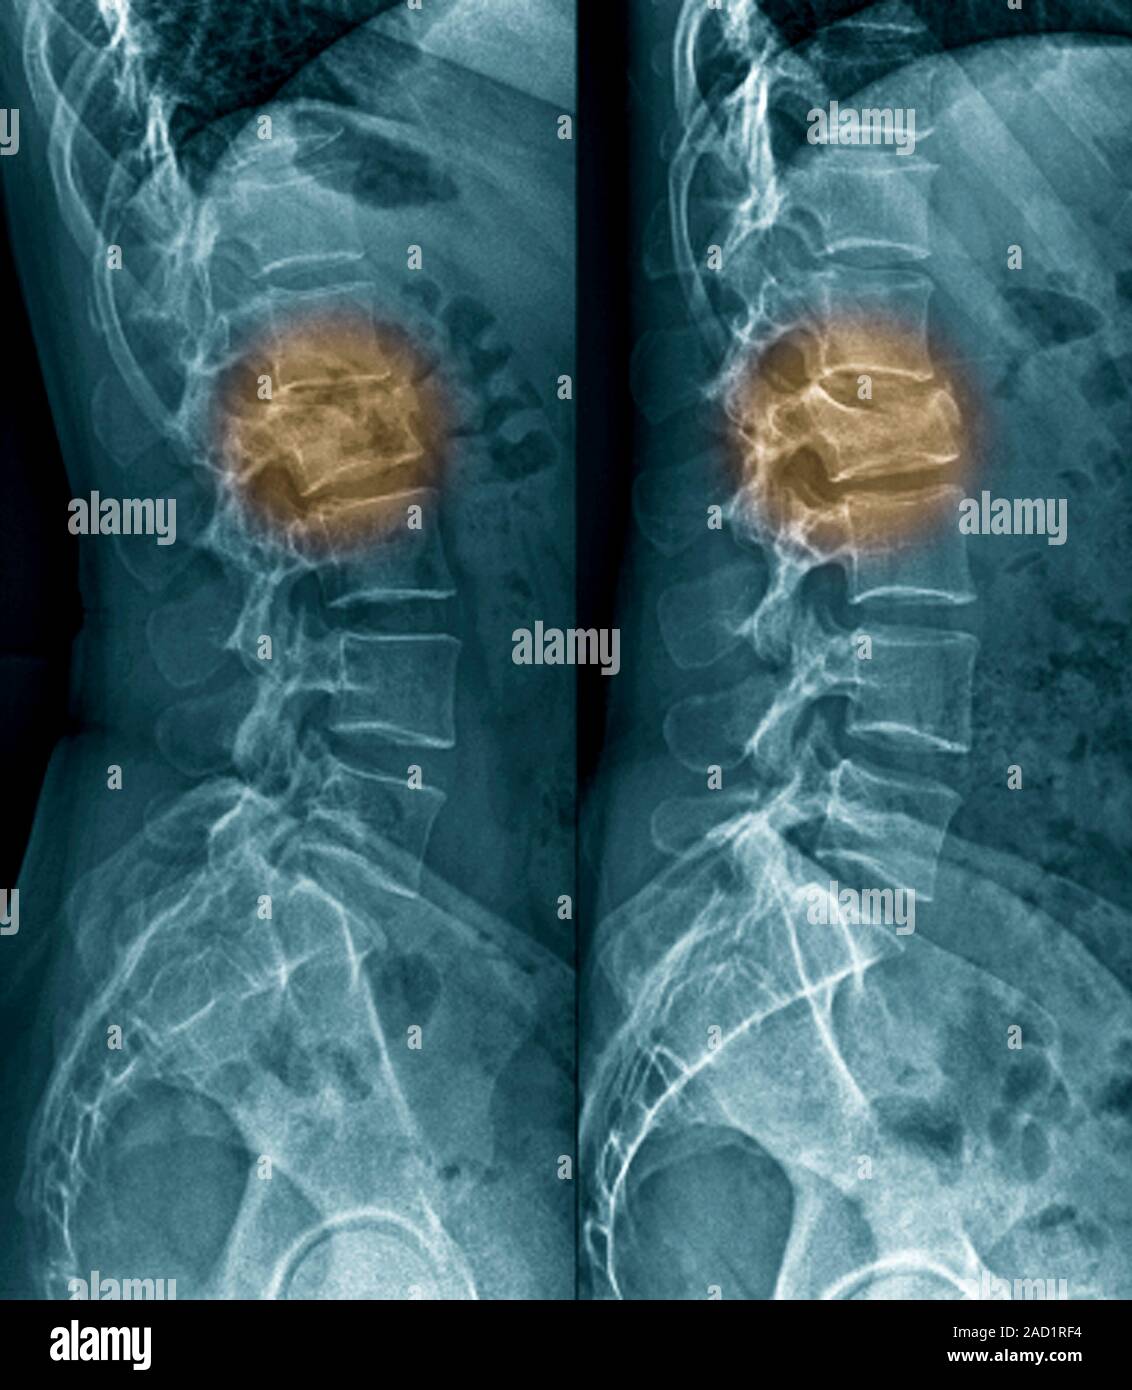

From www.alamy.com

Untreated fractured vertebra. Coloured Xrays of sections through the Compression Fracture Untreated Height loss can occur as the spine compresses and becomes shorter. A compression fracture typically occurs in the. Vertebral compression fractures (vcfs) of the spinal column occur secondary to an axial/compressive (and to a lesser extent, flexion) load with. A compression fracture is a type of broken bone that can cause your vertebrae to collapse, making them shorter. Compression fractures. Compression Fracture Untreated.

Untreated fractured vertebra. Coloured Xrays of sections through the Compression Fracture Untreated This often happens to the front of the vertebrae but not the back,. Vertebral compression fractures (vcfs) of the spinal column occur secondary to an axial/compressive (and to a lesser extent, flexion) load with. A compression fracture is a type of broken bone that can cause your vertebrae to collapse, making them shorter. A compression fracture typically occurs in the.. Compression Fracture Untreated.